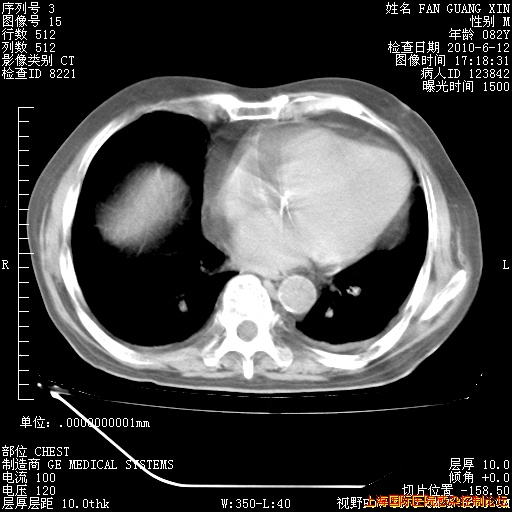

今天复查CT

整整相隔30天的肺部CT好像有所好转啊。甲强龙减量第3天,需要观察体温。

海管,自昨日你和我通完话后,不知您岳父消化道症状有无缓解?体温怎样?阅读7.12日胸部ct,个人认为目前激素治疗是有效的,甲强龙减量是适宜的。因在抗痨治疗,需密切观察肝功、肾功能和血常规。不过,老年、长期住院和大量使用激素,很担心菌群失调发生